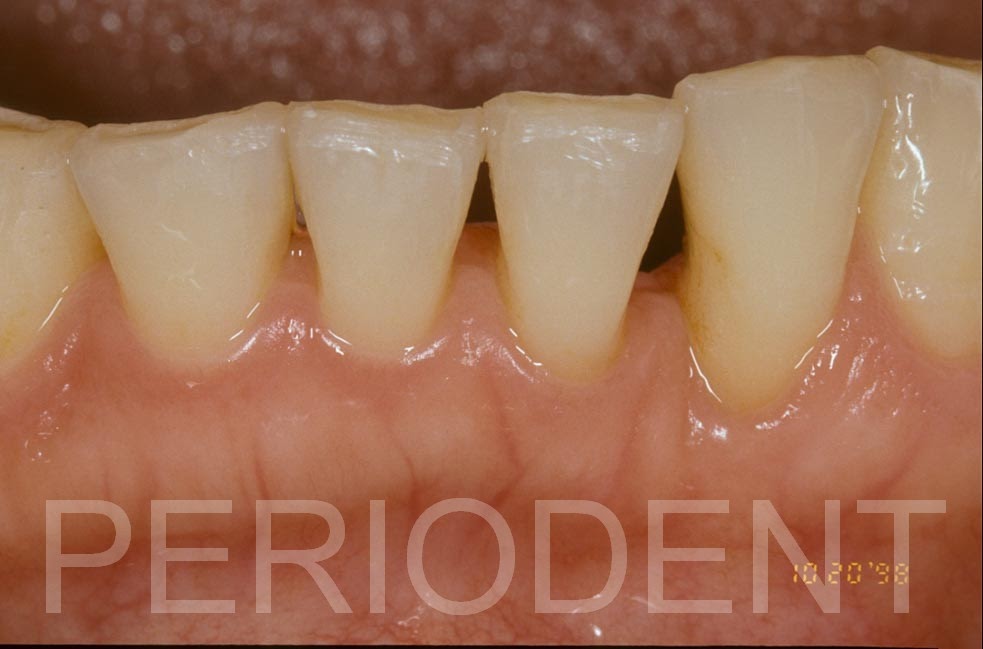

1998年矯正治療結束後